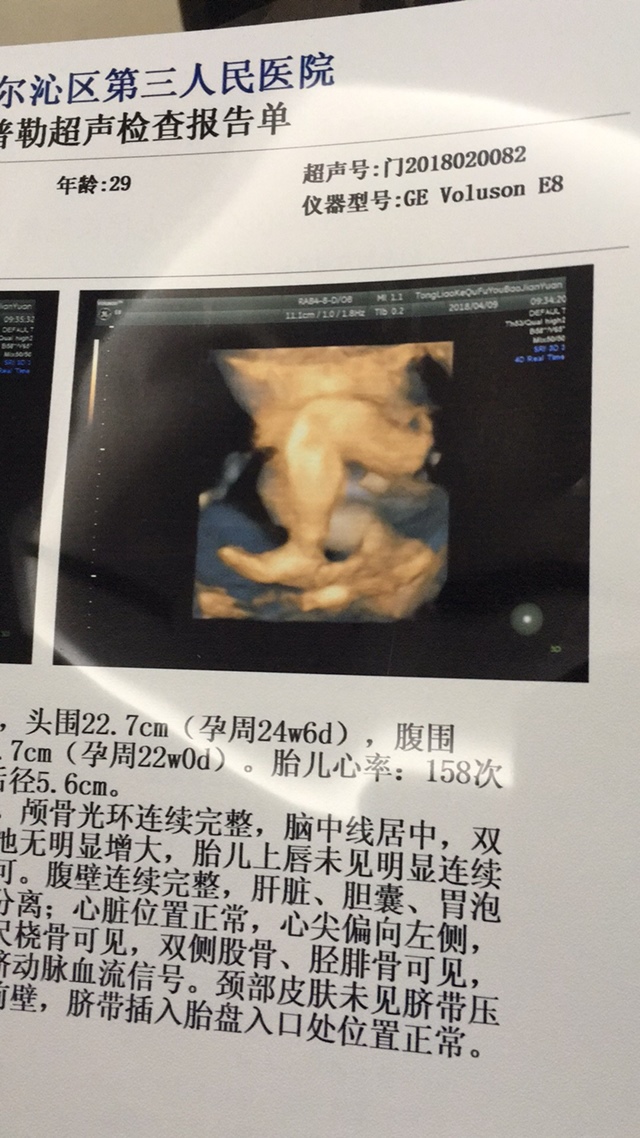

据说,单子右侧quel high1是女孩,2是男孩,只是听说的,但你如愿

女宝吧

女宝